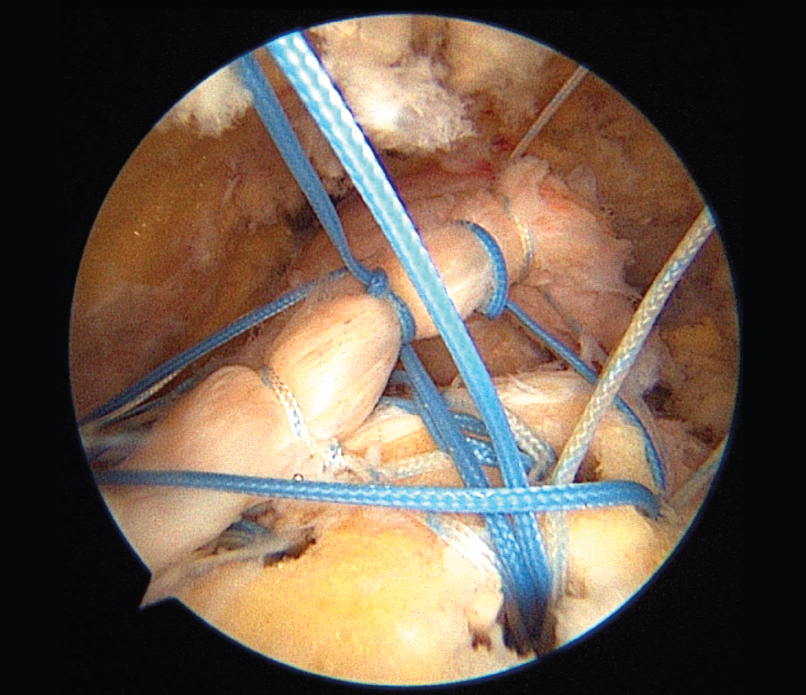

Reparación de manguito rotador con técnica de doble hilera

Rotator cuff repair with double-row technique

- Reparación de manguito rotador con técnica de doble hilera